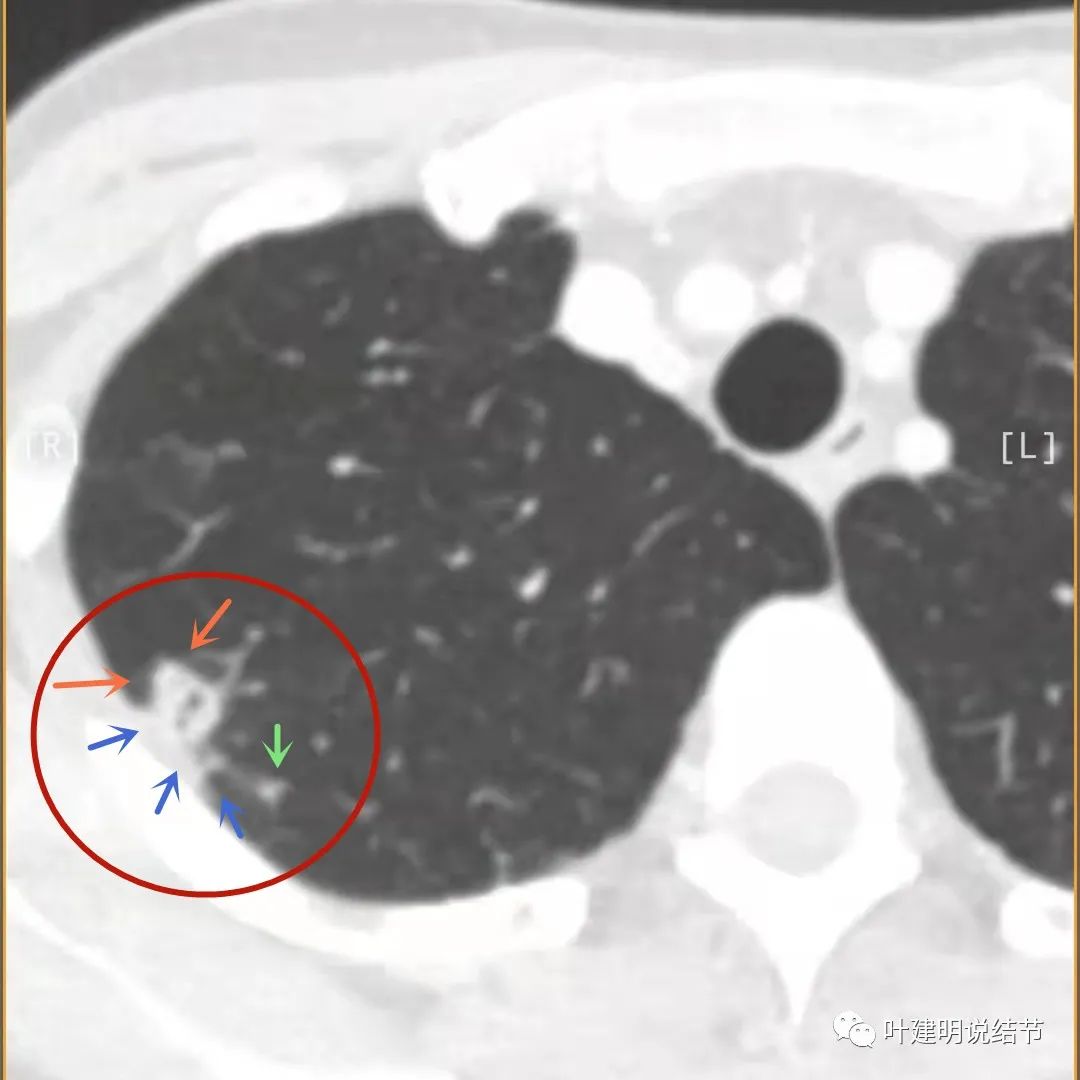

下面是今年复查的平扫片子,来看看有什么变化:

病灶邻近胸膜异常增厚(蓝色箭头)

有卫星灶(绿色箭头),邻近胸膜明显增厚,且模糊,边不清

邻近胸膜增厚

主病灶此层面似三角形,邻近胸膜增厚(蓝色箭头),结节实性部分密度较高(粉色箭头),边缘显模糊(砖色箭头)